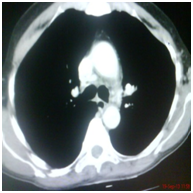

Sixty five year old gentleman is brought to emergency department with acute breathlessness. He had been symptomatic for last three months. He complained of persistent non productive cough followed by some hoarseness and lately breathlessness which was progressive in nature. He had been a current smoker with 25 pack years of smoking. He was hypoxemic on room air and was unable to lie flat. He denied symptoms consistent with COPD prior to his present illness lasting for three months. Routine blood chemistry was unremarkable. Echocardiogram showed normal left and right heart functions. Arterial blood gas revealed pH; 7. 35, PaCO2 of 45mmHg and PaO2 of 60mmHg of on 5LPM oxygen through simple mask. Chest diagram Figure 1 showed normal lung fields with normal hila, tracheal and cardiac contours. Injectable antibiotics, steroid, nebulised bronchodilators were started along with oxygen and non invasive ventilation. After two days of treatment he showed signs of improvement and was comfortable most of the times and tolerated removal of BiPAP for few hours. However, he preferred to maintain sitting posture even when in sleep and resisted lying down on the bed. He was noted to have paroxysmal respiratory distress requiring top-up nebulisation and reinstitution of NIV support and these events continued for next few days. Further imaging was planned in view of this unusual behaviour. Contrast enhanced CT scan of thorax was performed. Right paratracheal tumor was noted with extrinsic compression on trachea (Figure 2A-2C). Malignant growth obstructing trachea as the cause of his symptoms was discussed with the family. Bronchoscopy and stenting with involved risks were explained and informed and written consent was obtained. Videobronchoscopy was performed. Left vocal cord was immobile (Figure 3A). Subglottic trachea was circumferentially encroached by fleshy growth reducing the diameter to almost pin-hole size (Figure 3B & 3C). As bronchoscope was passed beyond the narrowed part the upper and mid tracheal lumen was wide open however encroached on both sides by infiltrating tumor (Figure 3D). Lower third trachea, primary carina and bronchi on both sides were wide and clear (Figure 3E). The dimensions were estimated and 6. 0cm hybrid Nitinol stent was placed in the trachea covering the tumor extension on both ends (Figure 4). Bronchoscope was withdrawn and patient breathed comfortably even in lying down position. Oxygen and BiPAP support were not needed anymore. Nebulization frequency was reduced and also the dose of steroid. Biospy from growth was consistent with moderately differentiated squamous cell carcinoma. He was discharged with advice to follow up with oncology for chemotherapy.

Figure 2a CT Scan: Right Paratracheal Mass.

Figure 2b CT Scan at level of carina.

Figure 2c CT Scan at level of carina.